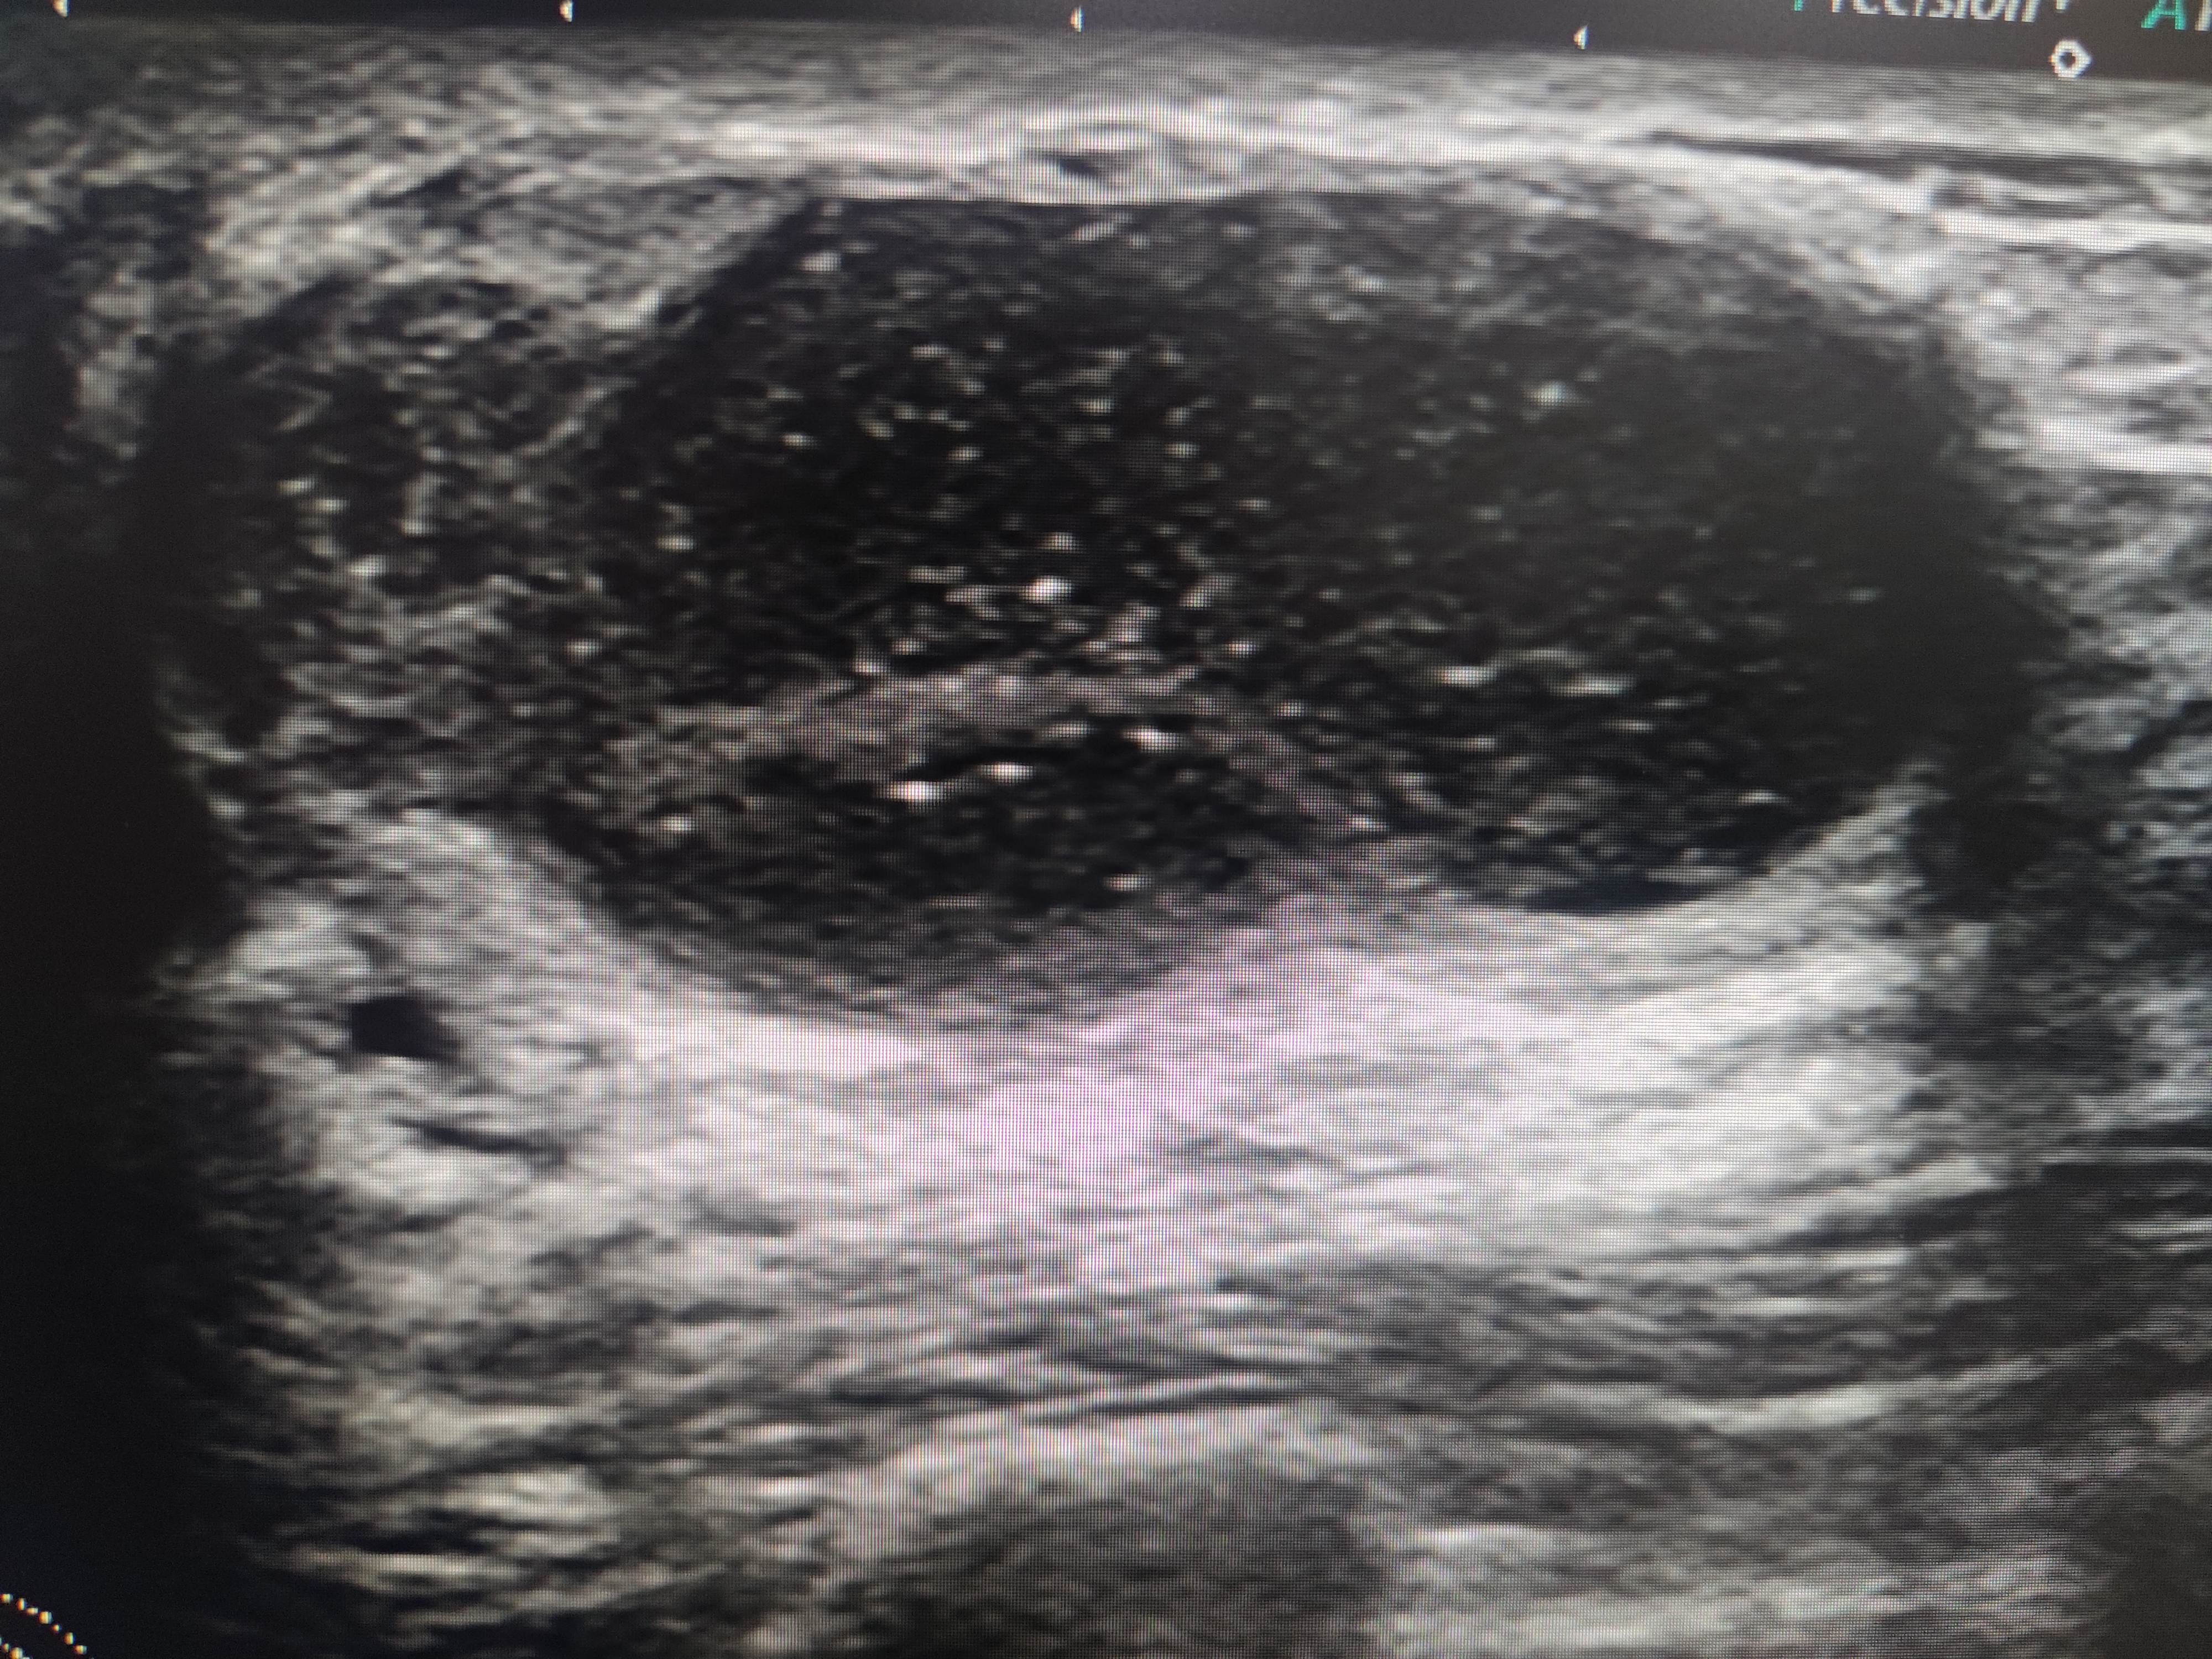

右侧乳腺12点乳晕后方腺体内可见一低回声包块,大小37✖️16mm,边界清,壁厚,内回声不均,可见数个彗星尾。来看看图,你们觉得该分几类?考虑是什么?